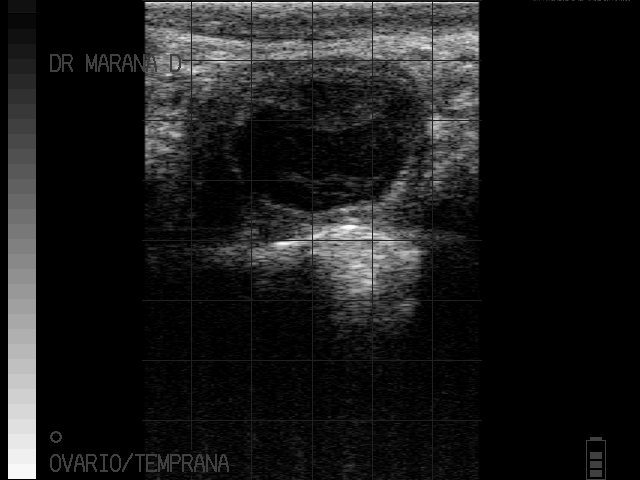

Quiste

Piometra